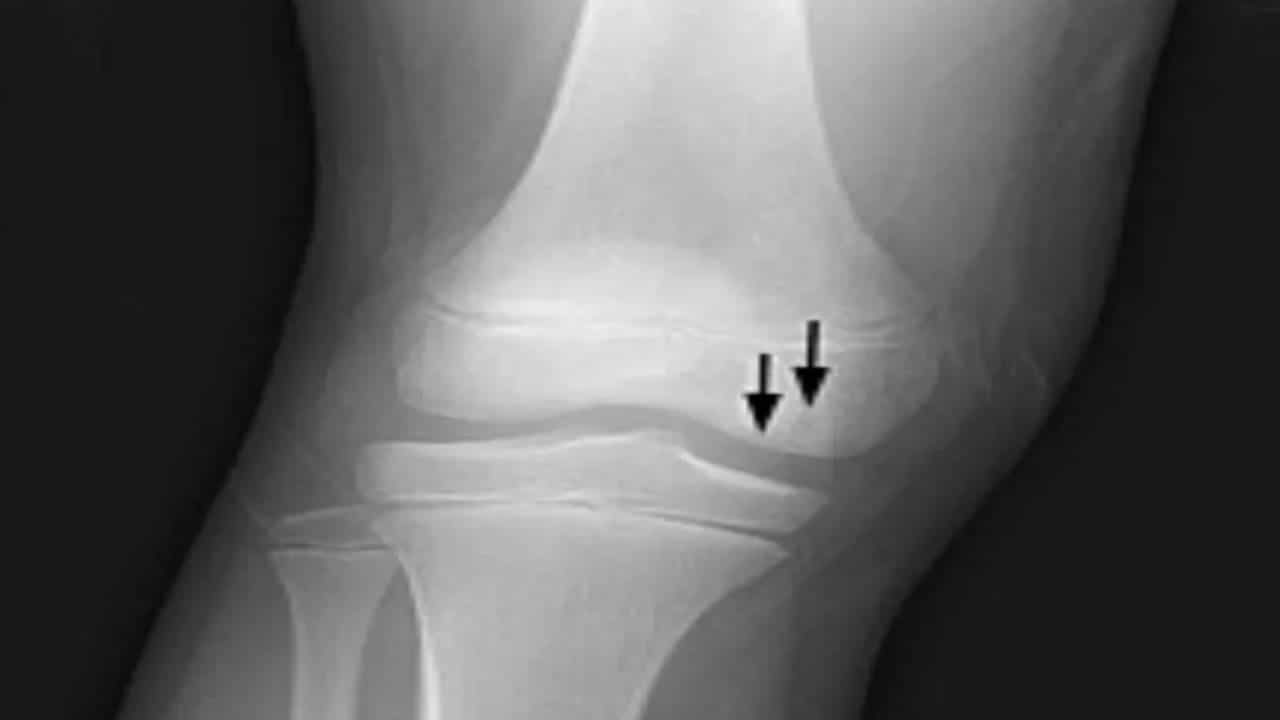

कोविडनंतर अनेकांना सांधेदुखी आणि हाडं दुखण्याचा त्रास होत आहे. लोकांना ही सामान्य समस्या किंवा संधिवाताचे लक्षण वाटत आहे, पण असे नाहीये. बऱ्याच प्रकरणांमध्ये रुग्णांना ॲव्हॅस्क्युलर नेकरोसिस (Avascular necrosis)हा रोग देखील होत आहे. सेंटर फॉर नी अँड हिप केअरचे वरिष्ठ प्रत्यारोपण सर्जन डॉ. अखिलेश यादव सांगतात की, ॲव्हॅस्क्युलर नेकरोसिस हा एक असा आजार आहे ज्यामध्ये हाडांचे टिश्यू (bone tissue)मृत होऊ लागतात, ज्यामुळे हाडं (bones)कमकुवत होऊ लागतात.

जेव्हा हाडांच्या टिश्यूपर्यंत रक्त पोहोचत नाही, तेव्हा अशा परिस्थितीत या आजारामुळे धोका निर्माण होऊ शकतो. हा आजार कोणत्याही वयात होऊ शकतो, मात्र सहसा 20 ते 60 या वयोगटातील लोकांना याचा त्रास होतो. ज्या लोकांना आधीच मधुमेह, एचआयव्ही/ एड्सचा हा आजार आहे, त्यांनाही आहे, त्यांनाही ॲव्हॅस्क्युलर नेकरोसिस आजार होण्याचा धोका असतो.

कोव्हिड नंतर या आजाराच्या केसेसमध्ये लक्षणीयरित्या वाढ झाली आहे. ॲव्हॅस्क्युलर नेकरोसिस हा आजारा काही व्यक्तींचे कोपर आणि सांध्यामध्येही होऊ शकते. या आजाराची लक्षणे वेळीच ओळखून त्यावर उपाय करणे गरजेचे आहे अन्यथा या आजरामुळे हाडांचे संपूर्णपणे नुकसान होऊ शकते.